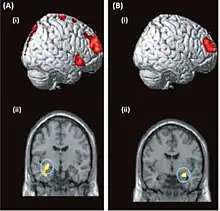

Brain-imaging data from two patients with dissociative amnesia

Brain activity can be assessed functionally for psychogenic amnesia using imaging techniques such as fMRI, PET and EEG, in accordance with clinical data.[6] Some research has suggested that organic and psychogenic amnesia to some extent share the involvement of the same structures of the temporo-frontal region in the brain.[7] It has been suggested that deficits in episodic memory may be attributable to dysfunction in the limbic system,[21] while self-identity deficits have been suggested as attributable to functional changes related to the posterior parietal cortex.[3] To reiterate however, care must be taken when attempting to define causation as only ad hoc reasoning about the aetiology of psychogenic amnesia is possible, which means cause and consequence can be infeasible to untangle.[15]